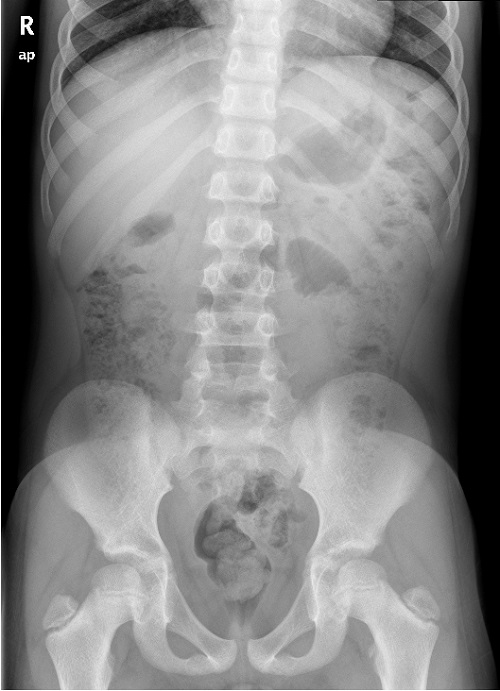

No presentaba síntomas gastrointestinales y su curva ponderoestatural era normal. Fue valorado previamente por Psiquiatría, donde se consideró que el paciente manifestaba un trastorno de la conducta alimentaria en posible relación con ansiedad. Aun así, se remitió a la sección de Gastroenterología Infantil para descartar causas secundarias. Se realizó una radiografía de abdomen simple, que descartó la presencia de un bezoar ( Fig. 2), y un análisis de sangre, con hallazgos compatibles con anemia ferropénica (hematíes: 4,68 × 10 6/μl, hemoglobina: 9,1 g/dl, hematocrito: 29,7%, hemoglobina corpuscular media: 19,4 pg, volumen corpuscular medio: 63,4 fl, concentración de hemoglobina corpuscular media: 30,7 g/dl, banda de distribución de hematíes: 21,1%, ferritina: 5 ng/ml, hierro: 25 μg/dl). Por refractariedad a la ferroterapia oral, se realiza serología de celíaca.